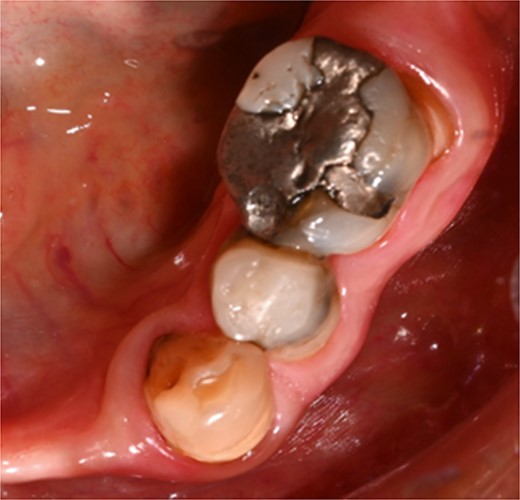

A 59-year-old male patient presented with a complaint of pain while biting on his lower left posterior teeth. Clinical examination revealed an extensive amalgam restoration on the lower left first molar (tooth 36) with a fractured restoration and secondary caries on the lingual aspect. The tooth was non-responsive to thermal testing and electrical pulp sensibility testing (EPT) and was tender to percussion. Radiographic examination showed radiolucency beneath the restoration on the mesial root surface, indicative of caries, along with furcation involvement and peri-radicular radiolucency. The tooth was diagnosed with pulpal necrosis and symptomatic apical periodontitis associated with extensive root caries (Fig. 6 and 7).

Clinical photograph of tooth 36 showing extensive amalgam restoration on mesio-occlusal-disto-bucco-lingual (MODBL).